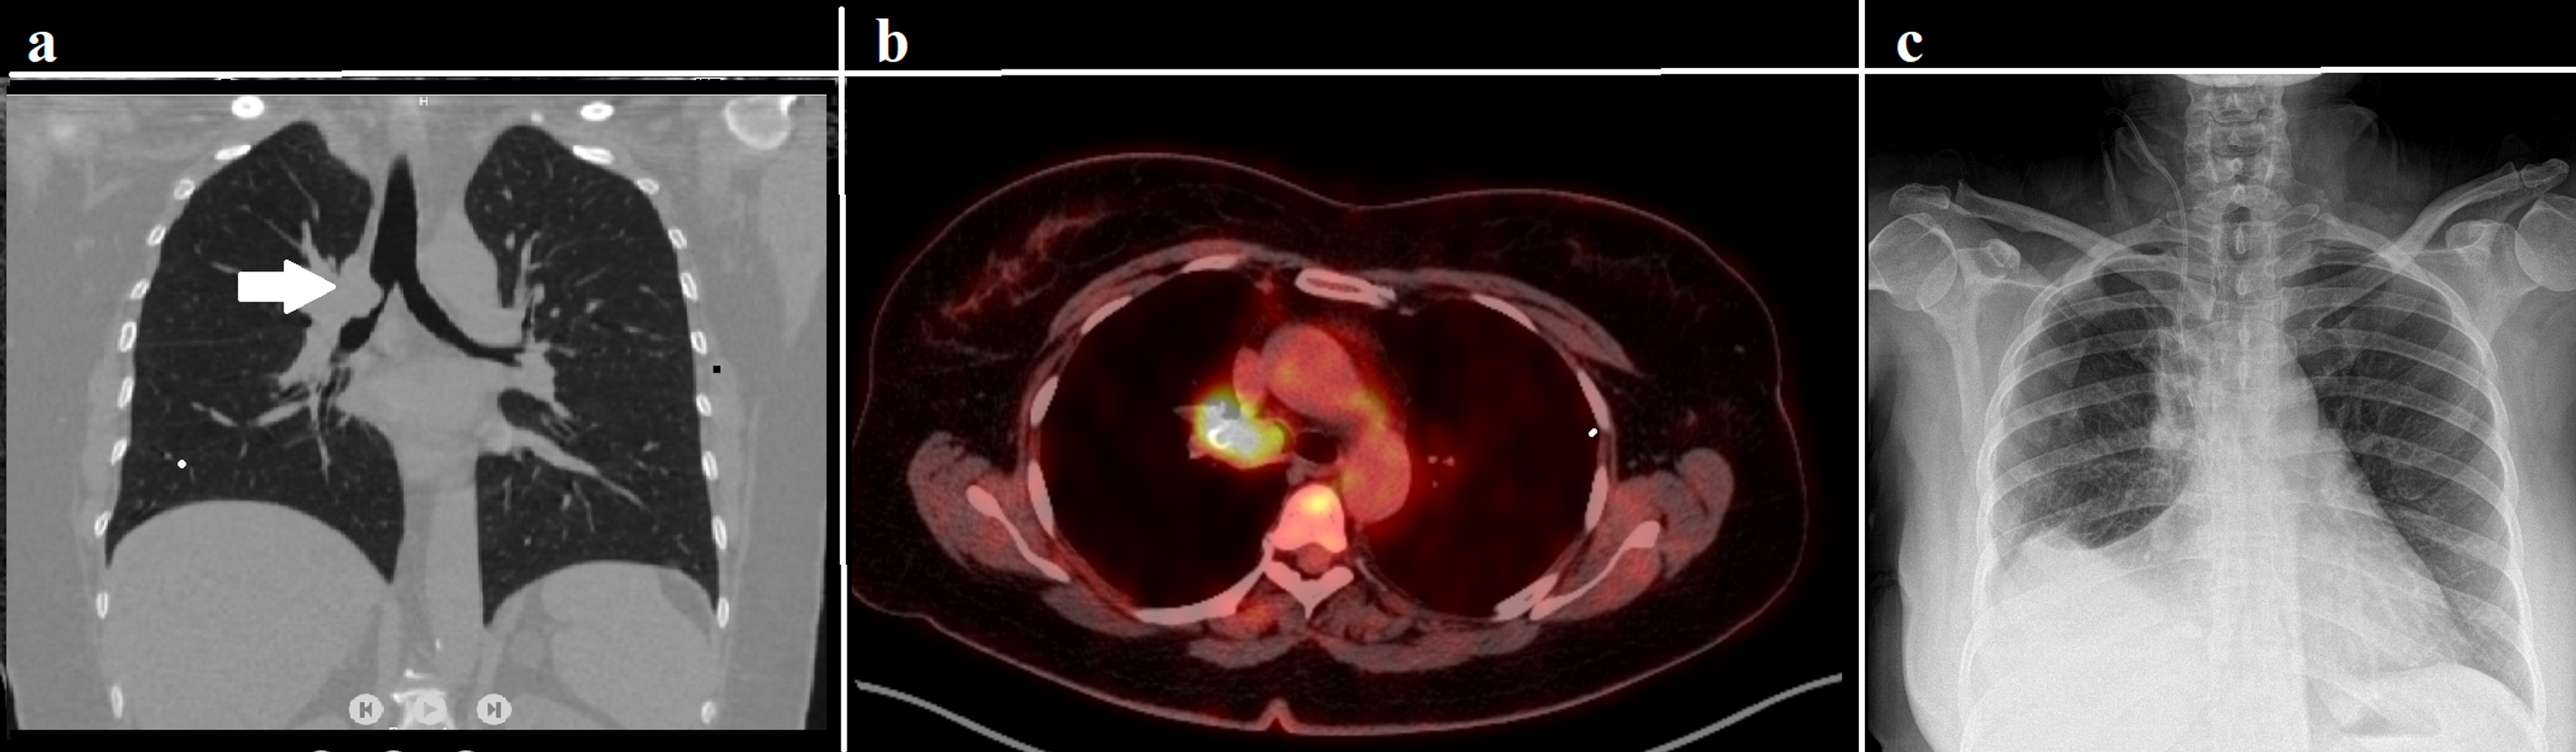

From www.cureus.com

Cureus Videothoracoscopic Bronchial Sleeve Resection for NonSmall What Is A Sleeve Resection Lung Standard sleeve resection refers to the circumferential removal of a segment of the main bronchus in continuity with a lobectomy in. Pulmonary sleeve resection is a type of complex lung resection and reconstruction surgery typically performed for patients with locally advanced lung cancer that involves. A lobe of the lung is removed. Segmental resection a small portion of the lung. What Is A Sleeve Resection Lung.

From www.jtcvs.org

Pulmonary sleeve resection in locally advanced lung cancer using What Is A Sleeve Resection Lung Pulmonary sleeve resection (psr) is a broad term to describe circumferential excision of a part of the bronchus and/or pulmonary vessels during. Segmental resection a small portion of the lung is removed following anatomical lines. Pulmonary sleeve resection is a type of complex lung resection and reconstruction surgery typically performed for patients with locally advanced lung cancer that involves. Standard. What Is A Sleeve Resection Lung.

Cureus Videothoracoscopic Bronchial Sleeve Resection for NonSmall What Is A Sleeve Resection Lung The entire lung is removed. Segmental resection a small portion of the lung is removed following anatomical lines. Pulmonary sleeve resection is a type of complex lung resection and reconstruction surgery typically performed for patients with locally advanced lung cancer that involves. A lobe of the lung is removed. Pulmonary sleeve resection (psr) is a broad term to describe circumferential. What Is A Sleeve Resection Lung.